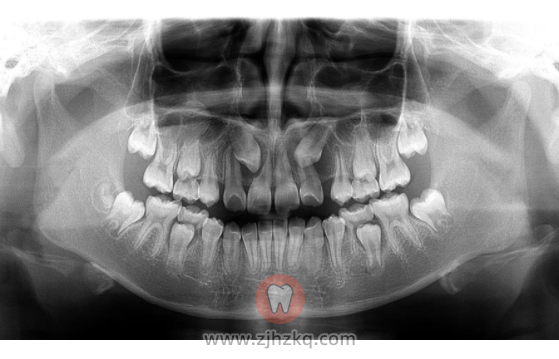

来杭州嘉德口腔,带给医生检查后,发现孩子的牙齿萌出间隙不够,拍片后发现果然有2颗牙齿还埋在颌骨里。除了萌出空间不足之外,牙齿长的方向也有点不对,斜着长了,还顶到了旁边牙齿,引起门牙牙根吸收。

历时三年,原本埋在颌骨里的牙齿都被牵引出来,重见天日,同时牙齿也被排列得整整齐齐,球球又恢复了自信爽朗的笑容。